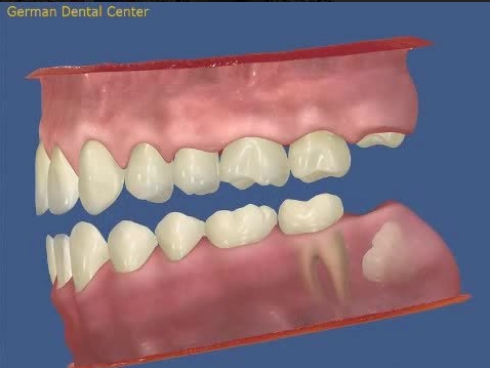

- Исправление прикуса